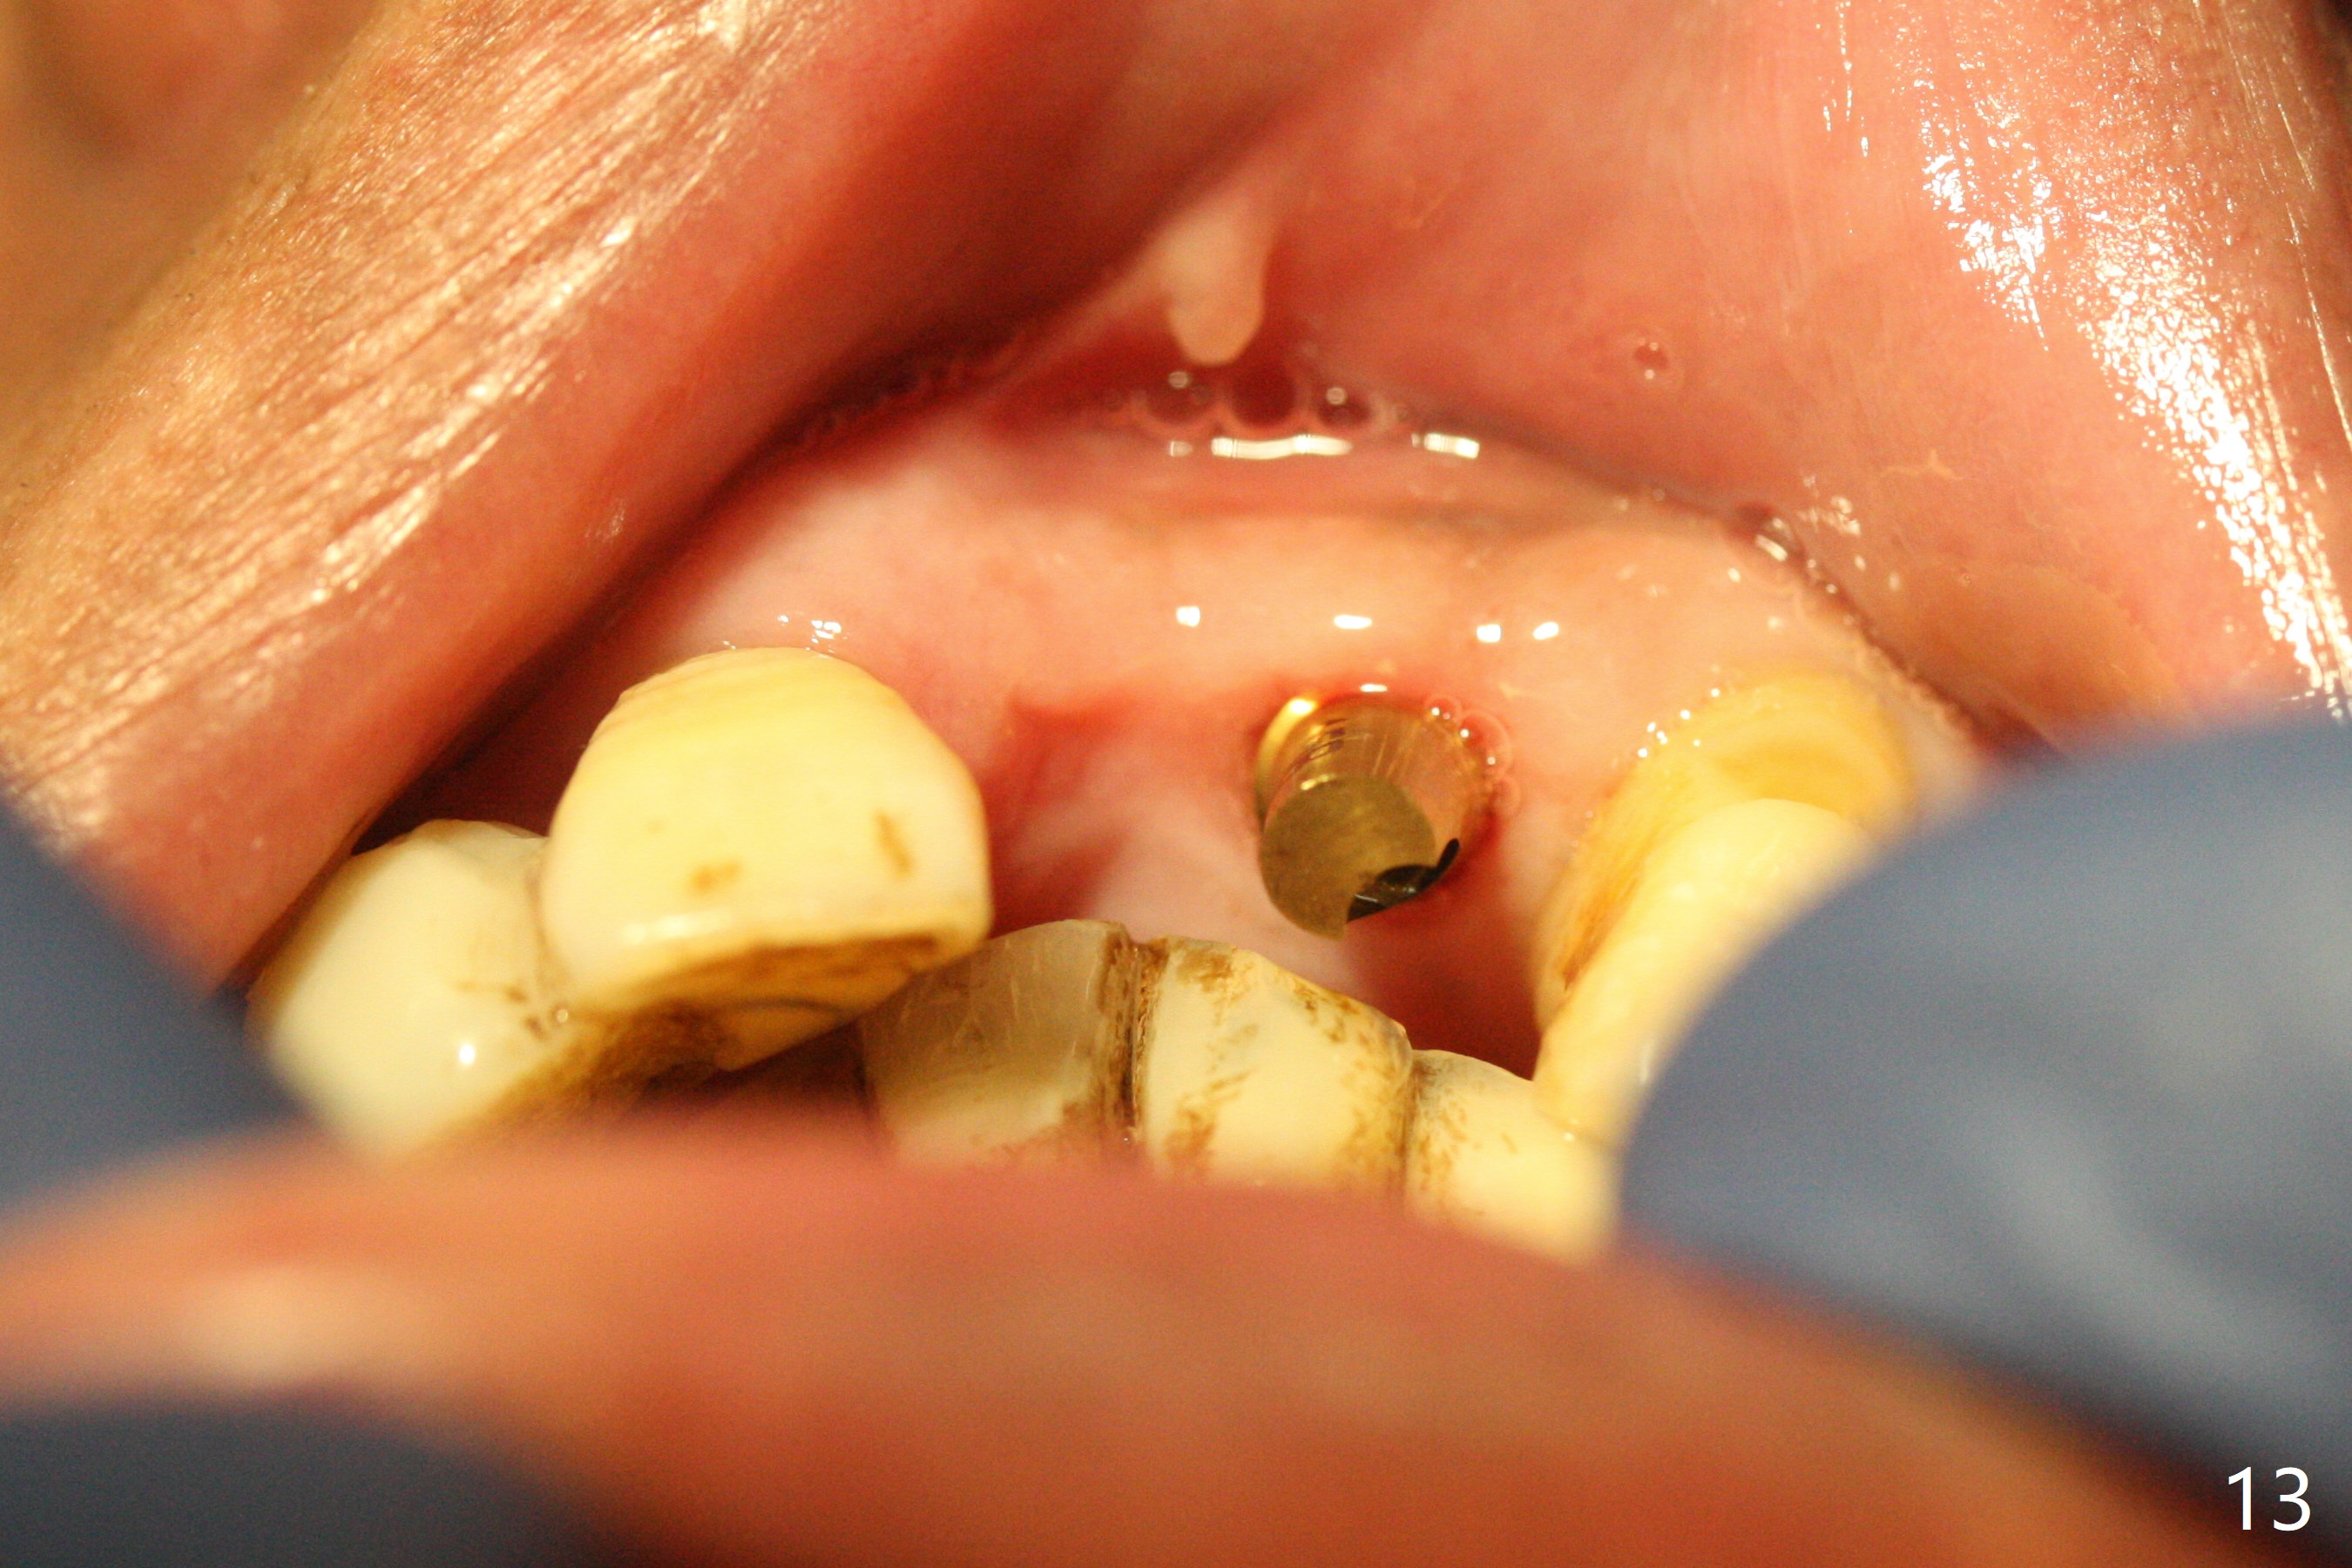

After a 4x10 mm implant is placed with fixture mounting (Fig.2 M) following sinus lift (*) at #12, osteotomy is initiated at #10 (Fig.1 (T: tube of surgical guide)). It appears that the drill (D) has good trajectory (between the Incisive Canal (red dashed line) and the canine root). The final position of the implant at #10 is acceptable (Fig.3). The implant at #12 is placed deeper (Fig.4 (arrow), as compared to Fig.2) because of clinically buccal superficial placement. The most critical challenge is anterior deep bite associated with posterior collapse. Periodontal dressing is applied. When the latter dislodges, there is minimal clearance for a provisional. Periodontal dressing is re-applied. The patient (smoker, partial edentulism with occlusal interference) returns for provisional nearly 1 month postop with chief complaint "something is lost in the back". In fact the healing abutment at #12 is lost with buccal granulation tissue (Fig.5). When a new abutment is seated, there is discomfort. When a healing screw is placed, it cannot be seated completely with two separate trials (Fig.6,7). Should we leave it as it is or open up for complete seating? It appears that the implant is loose. After preparation for clearance at #10, the abutment is retightened. It appears to turn with the underlying implant with discomfort. A 4x5 mm healing abutment is placed to reduce micro-movement. One week later, the infection at #12 dissolves with oral Amoxicillin (Fig.8). Due to limited occlusal clearance and implant tenderness when the abutment abutment is retightened, the cemented abutment is changed to a healing abutment. The implant at #10 seems to be osteointegrated, while the healing screw at #12 remains incomplete seating 3 months postop (Fig.9). The loose healing screw cannot be retightened securely, as there is bone loss around the implant 3 months postop (Fig.10 *). When a 4.5 mm x 15 degree 4 mm cuff angled abutment is placed, the mesiodistal trajectory improves (Fig.11), but there is no occlusal clearance (Fig.12). The latter would form when posterior support is established (Fig.13, either removable appliance (which the patient hates) or fixed one (finance)). Fig.14 shows the unhealed site of #12. Incision confirms the bone loss around the implant, which is removed. Although the sinus floor is absent, there is no membrane perforation. After debridement, allograft mixed with small amount of Osteogen is placed (Fig.15,16 G) and covered with Osteogen plug and 6-month membrane.